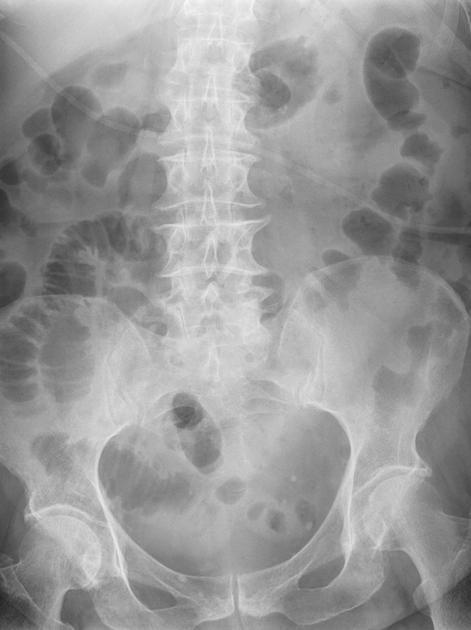

Image radiologique ASP du colite ischemique

est image de : Dilatation ileus du colon , Signe de

empreinte de pouce , intramural aerique dans cas necrose de

la paroi , image de croissante gaszeuse sous diapragmatique

dans cas perfore .

Image radiologique ASP

d'une colite ischemique : Image empreinte en

doigtier sur le colon trans verse et colon

descendant |